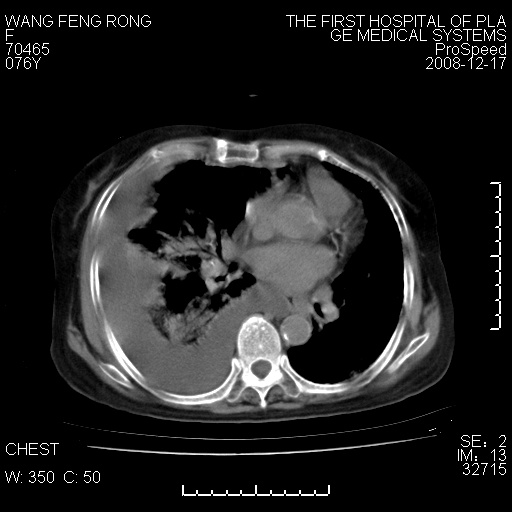

右肺大部实变,其内可见支气管影,但分支减少,宽窄不均,走行僵直,同侧胸腔大量积液;纵隔内见多发淋巴结影,但淋巴结大部有钙化;主动脉壁钙化;临床上病人咳嗽、消瘦。所以我考虑:1、结核(依据:右下肺实变,纵隔内淋巴结符合结核表现,同侧并发胸膜炎表现);2、支气管肺泡癌(依据:实变的肺组织内支气管分支减少,宽窄不均,走行僵直,没有把它放在第一诊断是因为没有看到明显肿大的淋巴结);3、动脉硬化(主动脉壁钙化就支持这个诊断)。

1)考虑两肺炎症感染;不排除肺泡癌可能。2)两肺间质纤维化。3)右侧胸腔积液。

病理结果,肺泡癌